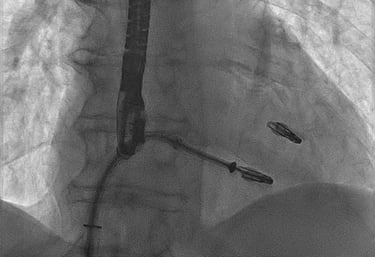

CORONAROGRAFIA

La Coronarografia è l’esame piu’ approfondito per valutare la presenza di restringimenti (“stenosi”) a carico delle arterie coronarie, ovvero delle arterie che nutrono il cuore. Viene effettuata tramite utilizzo di appositi cateteri che vengono inseriti attraverso l'arteria radiale o femorale. Per acquisire le immagini viene utilizzato un liquido chiamato “mezzo di contrasto” che opacizza il lume delle arterie mescolandosi al sangue. Le immagini vengono acquisite da un macchinario che emette una debole radiazione e registra le immagini.